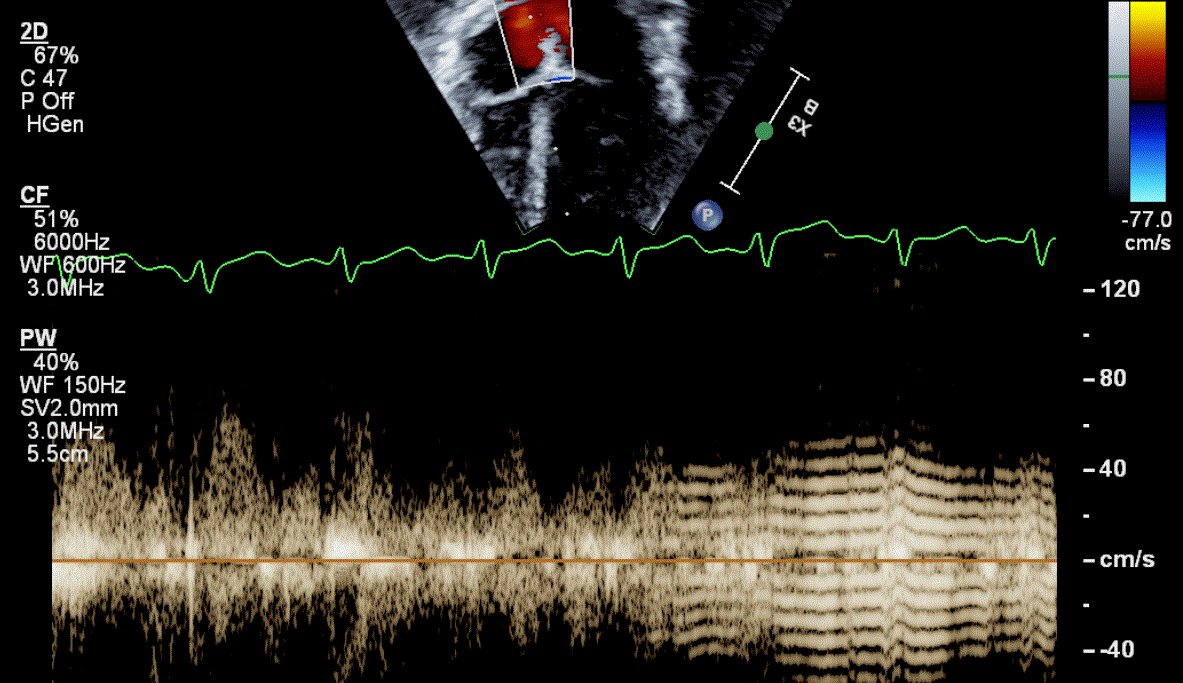

What is Wrong

Depth too shallow, need to decrease Depth so TAPSE is not running through EKG